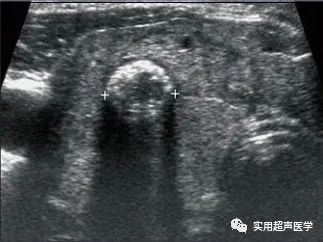

患者,女,77岁,桥本甲状腺炎合并甲状腺乳头状癌(FNA)。甲状腺右侧叶探及甲状腺肿大和实性重度钙化结节。